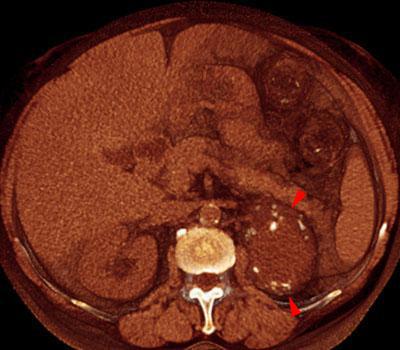

La ecografía, el TC y la RM son las exploraciones adecuadas para su estudio y la evaluación mediante TC debe incluir exploración simple y contrastada para valoración de pared, tabiques, calcificaciones y realce de los mismos sobre todo en los quistes renales complejos para ser incluidos en la clasificación de Bosniac: 1-2-2F-3 y 4 en orden a su benignidad, seguimiento y tratamiento.